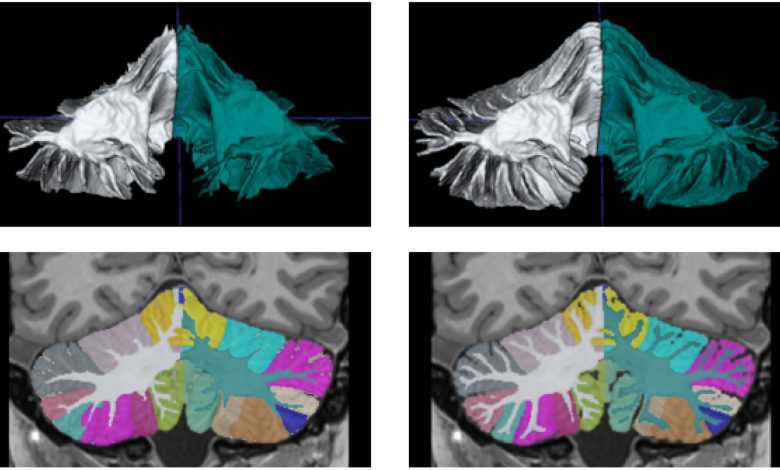

Esquerda: reconstrução 3D do rótulo WM e uma visão coronal da segmentação antes da correção semiautomática. Direita: reconstrução 3D do rótulo WM e uma visão de segmentação coronal após correção semiautomática. O WM “Arbor Vitae” é melhor definido na versão corrigida. Crédito: Neuroimagem (2025). Doi: 10.1016/j.neuroimage.2025.121063

O software Deepceres é capaz de medir 27 estruturas do cerebelo. E se destaca acima de tudo para melhorar a precisão da segmentação em comparação com o que é alcançado com os métodos usados até o momento, graças principalmente à aplicação de diferentes ferramentas de inteligência artificial.

“Usando imagens de ressonância padrão de 1 milímetro cúbico, elas são convertidas em imagens de resolução ultra alta de 0,125 mm3 Usando redes neurais profundas “, acrescenta o professor José Vicente Manjón, o principal pesquisador do projeto.

“Isso permite que pesquisadores e profissionais de saúde obtenham informações detalhadas sobre a anatomia do cerebelo sem a necessidade de dados de alta resolução na imagem inicial. É como ir de uma imagem em preto e branco para uma imagem colorida. Não há nada semelhante atualmente e, além disso, é acessível para toda a comunidade científica”.